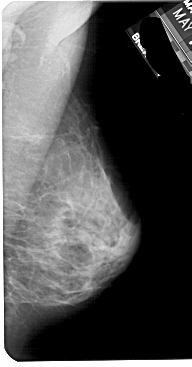

A_1888_1.RIGHT_MLO

LEFT_MLO LINES 5491 PIXELS_PER_LINE 2896 BITS_PER_PIXEL 12 RESOLUTION 43.5 OVERLAY

RIGHT_MLO LINES 5491 PIXELS_PER_LINE 2866 BITS_PER_PIXEL 12 RESOLUTION 43.5 NON_OVERLAY